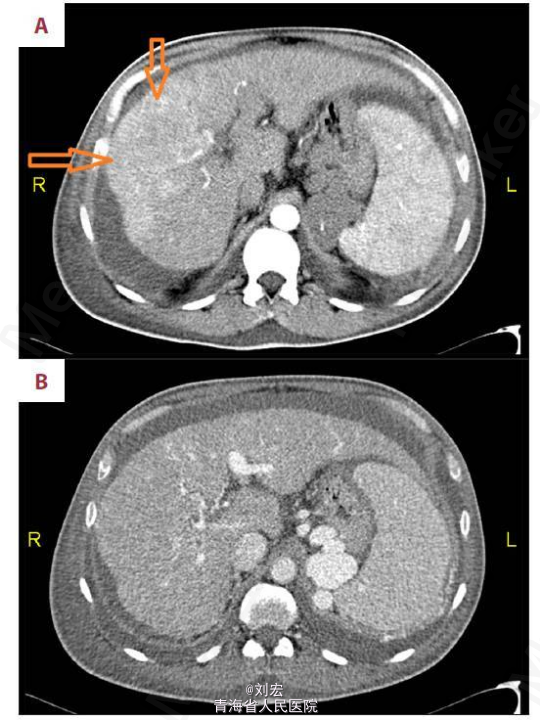

查体:右侧面部腮腺肿大,质硬伴轻压痛,肝脾肿大,移动性浊音阳性。辅查:腹部CT提示肝硬化、门脉高压和肝脏右叶的多中心肝细胞癌(图2)。颈部 CT 扫描提示右侧下颌角溶骨性破坏病灶(图3)。右侧腮腺切片活检和组织病理学检查,提示转移性肝细胞癌。